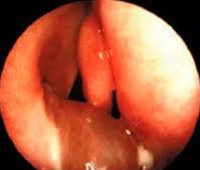

• Отоскопия. При объективном осмотре отоларинголог определяет наличие стойкой перфорации барабанной перепонки в периферической или центральной части, через которое происходит выделение гнойно-геморрагических патологических масс. После эвакуации последних в некоторых случаях в просвете дефекта выявляется образование красного или розового цвета.

• Отоэндоскопия. Осмотр барабанной полости при помощи эндоскопа дает возможность визуализировать структуру полипа. Определяется округлое, несколько подвижное образование с широкой основой или на ножке мягкой или уплотненной консистенции. Обнаруживается наличие ретракционных карманов барабанной перепонки, тимпаносклероз и тимпанофиброз, холестеатомный процесс, повреждения слуховых косточек и нарушения проходимости слуховой трубы.